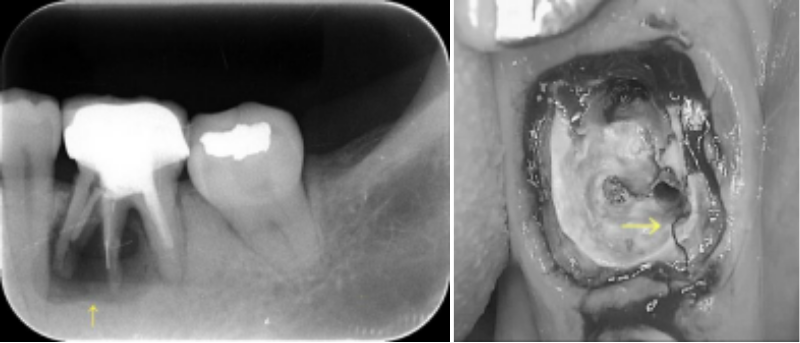

「根尖病巣」と言って、根っこの先に細菌感染由来の膿疱ができてしまいます。

初めは自覚症状がなくても、何年か経ってから突然激しい痛みが出てきたり、時折 ジーンと疼くことを繰り返すようになったりします。そうなると、再治療(再根管治療)が必要となったり、またひどい場合には抜歯となってしまいます。

① 虫歯で細菌感染した歯髄

② 一旦歯髄は歯髄腔内から全部取り除き、そこを無菌的状態にする

③ 幹細胞と成長因子の混合物を歯髄腔内へ入れる

④ 歯髄が再生する